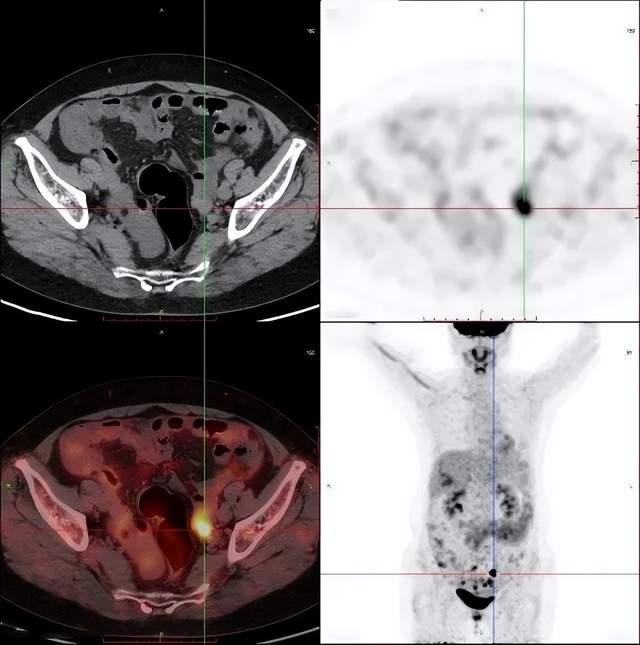

女性,60岁

相关病史:宫颈高级别鳞状上皮内病变(HSIL)锥切术后4月;否认结核及其他慢性病史。无其他临床症状。已绝经,无外伤史。2021-3-21日,患者因检查发现CA125渐进升高(250U/mL)后,在平安健康(检测)中心接受PET/CT检查。

PET/CT影像学表现

结论: 盆腔双附件区结节灶(左侧著)、右侧膈前上、肝脏包膜及腹盆腔多发结节灶、腹膜后多发淋巴结FDG代谢增高,考虑:卵巢癌(源于左侧卵巢可能性大)并上述部位多发转移瘤

PET/CT结论:

考虑:卵巢癌(源于左侧卵巢可能性大)

手术病理结果:

卵巢癌

对比结论:

PET-CT实现肿瘤的精准定位及确诊。